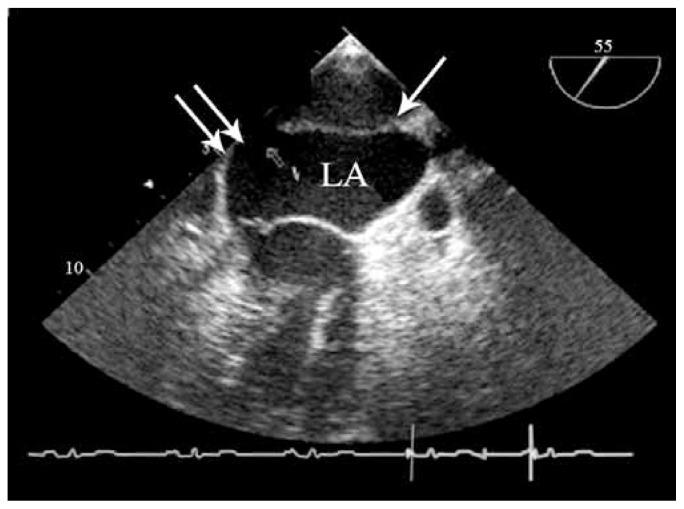

Cor triatriatum sinistrum is a rare congenital cardiac malformation, accounting for about 0.1-0.4% of all congenital heart diseases and characterized by the presence of a fibromuscular membrane that subdivides the left atrium into two chambers in the classical form. While classic cor triatriatum in most patients can be observed during the neonatal period or early infancy, it is very rare in adults.We herein present an incidental finding of cor triatriatum sinistrum in a middle-aged man with coronary artery disease scheduled for coronary artery bypass graft surgery. The patient was admitted for exertional dyspnea and chest pain of a three-month duration. He had a past medical history of mild hyperlipidemia and mild hypertension. Transthoracic two-D echocardiography (TTE) demonstrated a visible presence of a membranous band in the mid portion of the left atrium with obvious obstruction by color and Doppler flow measurements, confirmed by three-D echocardiography. Selective coronary angiography also revealed a severe ostioproximal stenosis of the left anterior descending artery of up to 99%.On-pump coronary artery bypass grafting was performed without complications, during which the anastomosis of the left internal mammary artery to the left anterior descending artery and the removal of the membrane were done.

左房三房心是一种罕见的先天性心脏畸形,约占所有先天性心脏病的0.1 - 0.4%,其典型表现为存在一个纤维肌性隔膜,将左心房分为两个腔室。虽然大多数患者的典型三房心在新生儿期或婴儿早期即可观察到,但在成人中非常罕见。我们在此报告一例在计划进行冠状动脉搭桥手术的中年冠心病男性患者中偶然发现的左房三房心病例。该患者因持续三个月的劳力性呼吸困难和胸痛入院。他有轻度高脂血症和轻度高血压病史。经胸二维超声心动图(TTE)显示左心房中部可见一条膜状带,通过彩色和多普勒血流测量显示有明显梗阻,三维超声心动图证实了这一点。选择性冠状动脉造影还显示左前降支近端严重狭窄达99%。在体外循环下进行冠状动脉搭桥手术,无并发症发生,术中完成了左乳内动脉与左前降支的吻合以及隔膜切除。